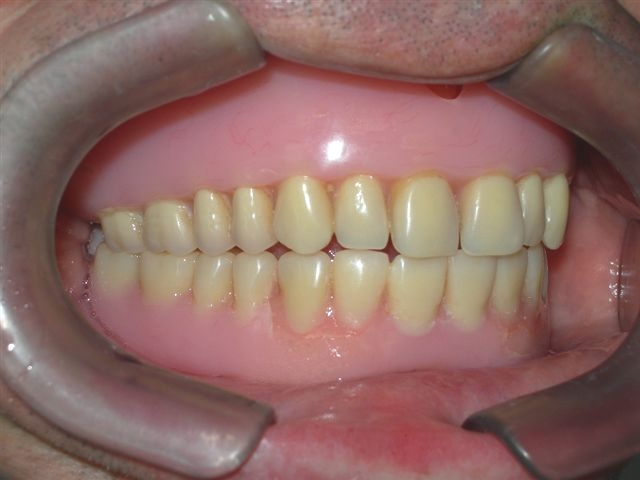

Vista interna da articulação entre as próteses antagonistas |